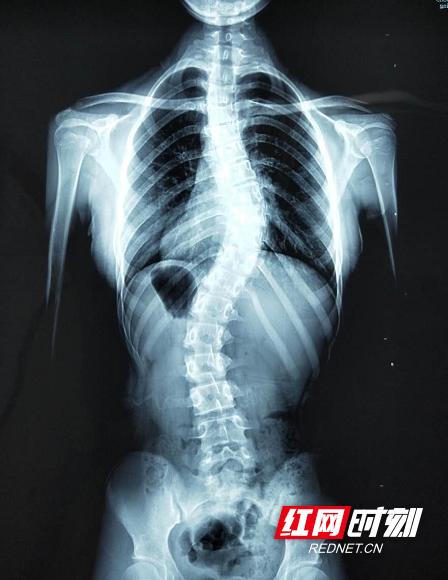

茜茜全脊柱X光影像。

茜茜在华医金良经过3个月连续治疗,脊柱弯曲度明显得到了改善:T5-T12 /CobbT=28°、T12-L4/CobbL=28°、右胸旋转10°、左腰旋转8°。